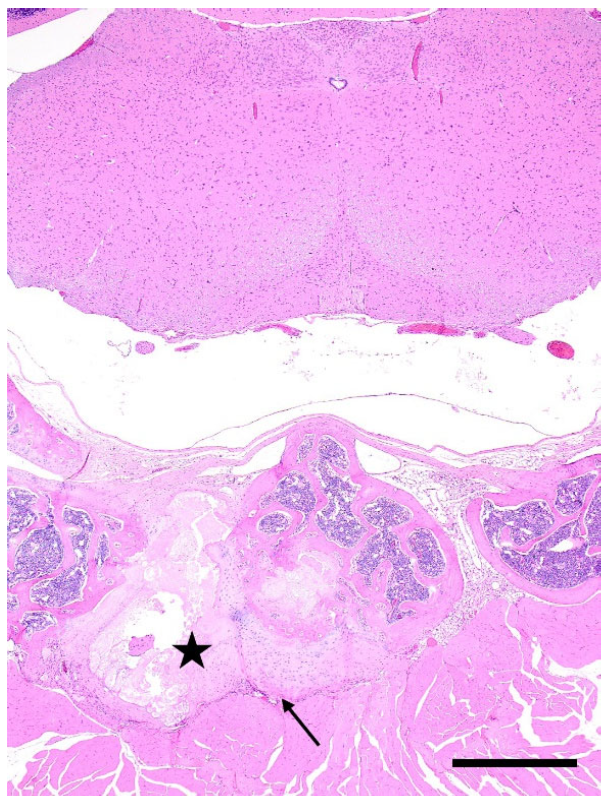

3.3. Blood Collection-Related Findings